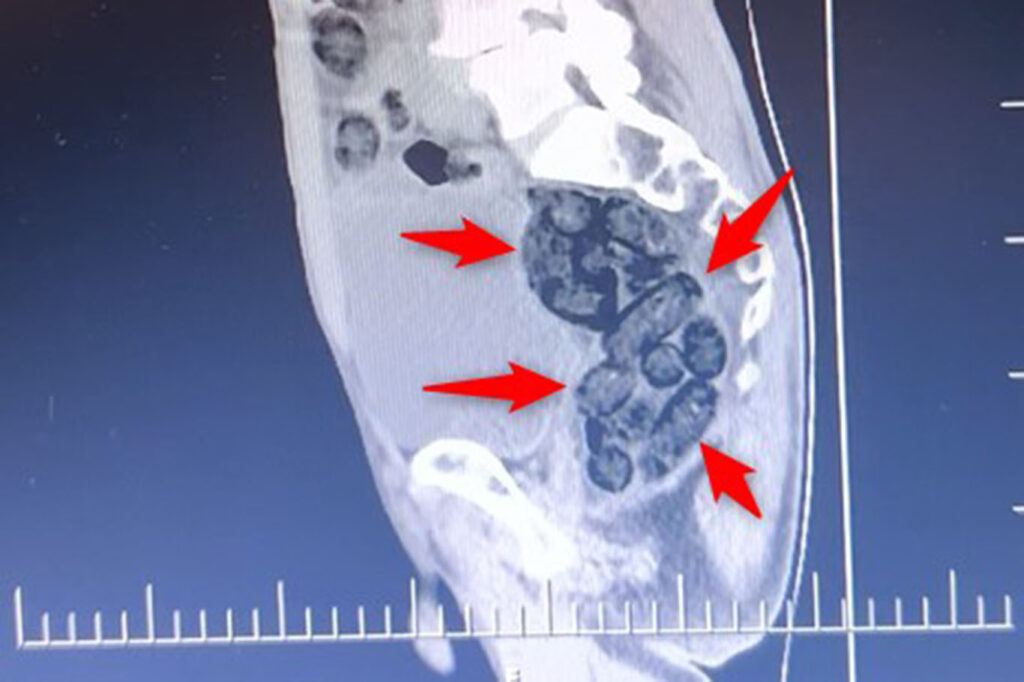

İl girişinde durdurulan bir otobüste yolcu olarak bulunan yabancı uyruklu bir şahıs üzerinde yapılan kontrollerde, şahsın midesinde 64 parça halinde toplam 472 gram metamfetamin maddesi tespit edilerek ele geçirildi.